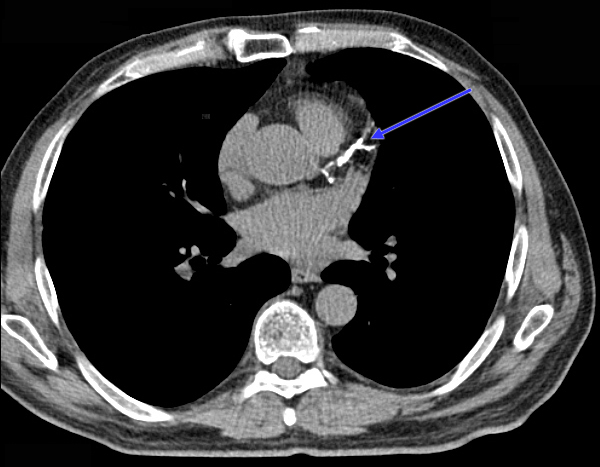

Ten Minutes that Could Save Your Life Coronary calcium scanning: a new way to look at your risk for heart disease

Each year, more than 800,000 Americans will suffer a heart attack. More than 150,000 will die before they experience their first symptom. Could they have been saved? A relatively new and effective way to screen people at risk for heart disease is called coronary calcium scanning. Calcium scanning has been around since the late 1990s, and started capturing people’s attention…